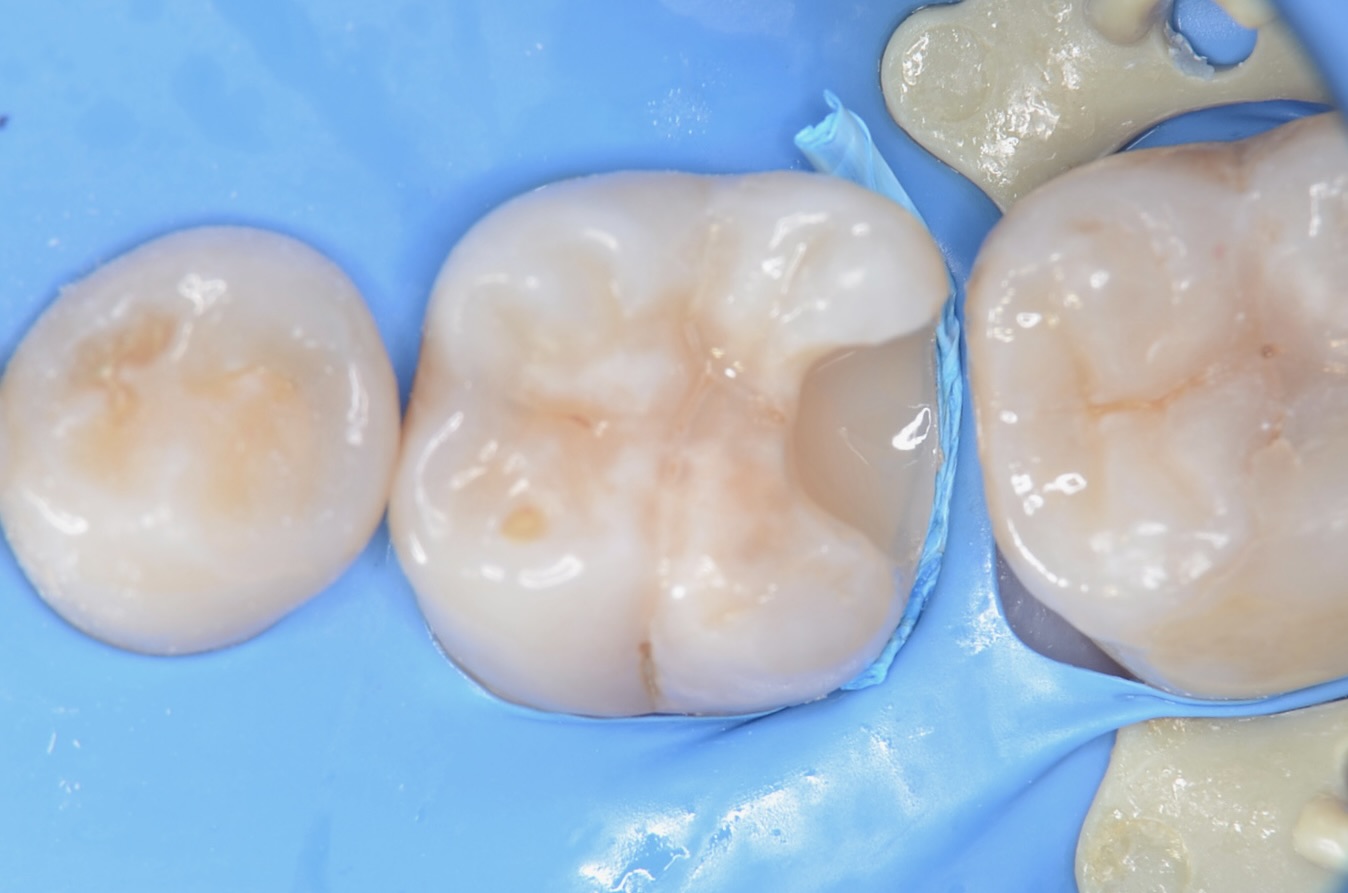

ラバーダム装着後、虫歯完全除去

虫歯治療においてもラバーダム装着は必須です。 唾液や血液から歯面が汚染されるのを防ぎ、乾燥状態を保つラバーダムは、接着力を向上させるためにも大切なアイテムです。 虫歯を完全に削りました。 -

レジン充填

青色のテフロンテープを紐状にしたものを歯肉溝に挿入しました。レジンが、ラバーダムに触れないようにするためです。一気にレジンを充填して硬化させるとレジンの重合収縮によりレジンが、歯から引き剥がされる力がはららいてしまうので。少量づつレジンを充填硬化させます。 -